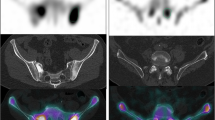

The total bone volume (TBV) and regional metabolic bone volume (MBV) were calculated for cervical spine to pelvis SPECT/CT images using the GI-BONE software (Nihon Medi-Physics Co. Ltd., Tokyo, Japan). Figure 1 shows the extracted TBV and total MBV and the bone metabolism volumetric index (BMVI) calculation process. TBV was defined as a region with a Hounsfield unit of > 120 and SUV of > 0.5, thereby eliminating radioactive urine and microcalcifications to improve the accuracy of TBV measurement. The mean SUV of the normal thoracic and lumbar spine in Japanese patients has been reported to be 4.4–4.6, and the SUV threshold value to detect abnormal uptake should be higher than 5 [19, 21]. Regional MBV was also similarly measured in four SUV levels, i.e., > 5, > 6, > 7, and > 8, with a Hounsfield unit of > 120, and the sum of each level was used as the total MBV. The BMVI was calculated as the percentage of the total MBV divided by TBV, that is, the volumetric index for the extent of bone disease. The variability of TBV measurement was evaluated using the percentage coefficient of variance (%CV) of TBV of each patient.

Figure 5 shows the results of serial BONENAVI and maximum intensity projection (MIP) images. PSA in Fig. 5b–d was significantly higher than that of the previous values, whereas ALP, BSI, and BMVI showed no obvious changes. Figure 5d, e seems to be almost identical with the extracted extent of bone metastasis, although the BMVI was higher than the BSI. Pelvic segmentation using the BONENAVI software showed overextraction below the ischial bone in all whole-body images (Fig. 5a–d) because of abnormal uptake of the right ischial bone. The abnormal uptake in the fifth lumbar vertebra was consistently interpreted by the physician as a degenerative change in all four bone scintigraphy. Extraction of the cervical spine in the MIP image (Fig. 5e) was also interpreted as a degenerative change.

Another advantage of using SPECT/CT images to detect abnormal uptakes would be to avoid anatomical overlap. Lesion detection on whole-body planar images may not be accurate because of bone-on-bone overlap, and bone overlap in the kidneys, ureters, and bladder containing radioactive urine, as well as radioactivity contamination [25]. Patients with prostate cancer often have difficulty voiding properly. In Fig. 5, if an abnormal uptake was observed in the sacrum, no detection would have been possible, because of the radioactive urine in the bladder. Furthermore, in Fig. 5a, urine in the renal pelvis was detected as a less likely malignant uptake in the left rib. The region may not be accurately extracted even on curved rib contours (Fig. 6e). Moreover, planar images have lower contrast than SPECT images, which cannot be corrected for attenuation, scatter, and blurring because of collimator apertures.